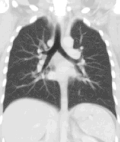

Lungs

A CT scan can be used for detecting both acute and chronic changes in the lung parenchyma, the tissue of the lungs.[41] It is particularly helpful because normal two-dimensional X-rays do not show such defects. A variety of techniques are used, depending on the suspected abnormality. For evaluation of chronic interstitial processes such as emphysema, and fibrosis,[42] thin sections with high spatial frequency reconstructions are used; often scans are performed both on inspiration and expiration. This special technique is called high resolution CT that produces a sampling of the lung, and not continuous images.[43]

Bronchial wall thickening can be seen on lung CTs and generally (but not always) implies inflammation of the bronchi.[44]

An incidentally found nodule in the absence of symptoms (sometimes referred to as an incidentaloma) may raise concerns that it might represent a tumor, either benign or malignant.[45] Perhaps persuaded by fear, patients and doctors sometimes agree to an intensive schedule of CT scans, sometimes up to every three months and beyond the recommended guidelines, in an attempt to do surveillance on the nodules.[46] However, established guidelines advise that patients without a prior history of cancer and whose solid nodules have not grown over a two-year period are unlikely to have any malignant cancer.[46] For this reason, and because no research provides supporting evidence that intensive surveillance gives better outcomes, and because of risks associated with having CT scans, patients should not receive CT screening in excess of those recommended by established guidelines.[46]